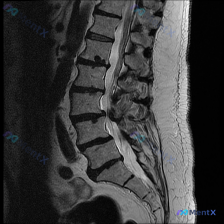

整理到一份腰椎MRI T2加权矢状位的影像分析资料,用户一开始关注的是「脊柱侧弯(Scoliosis)」,但仔细读下来,里面还有几个更值得讨论的影像表现: - 多节段(L2/3到L5/S1)椎间盘T2信号减低,「黑盘征」 - L4/5、L5/S1椎间盘突出,压迫硬膜囊,局部椎管狭窄 - L4、L5邻...